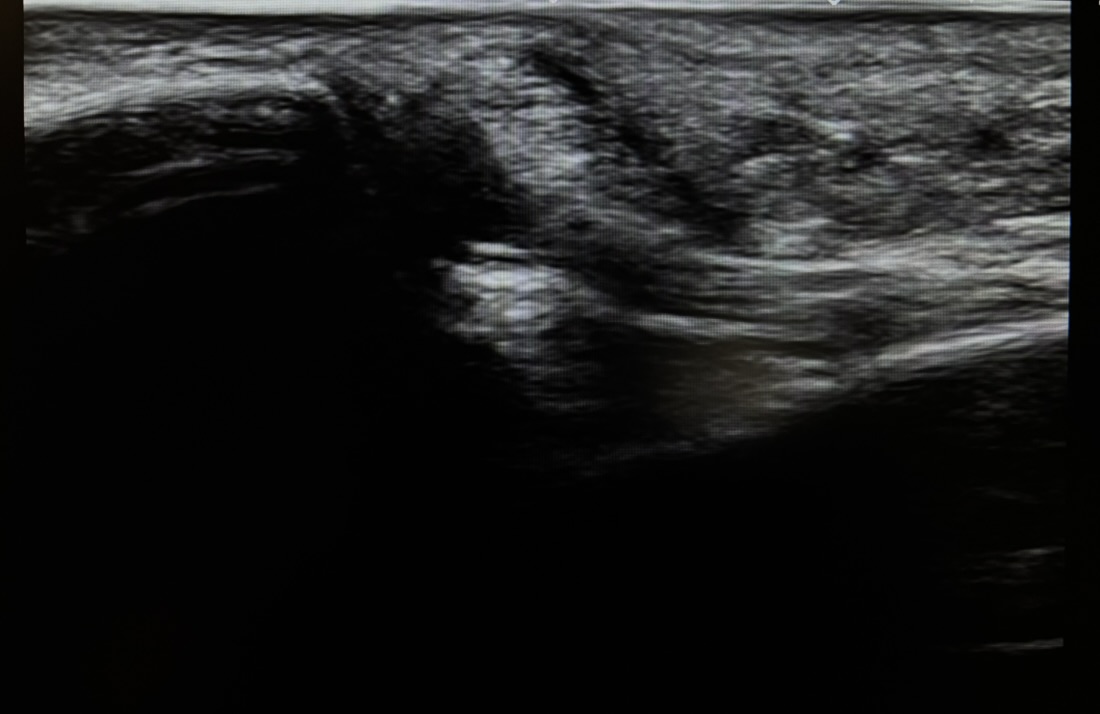

| 超音波画像観察(エコー) | ATFLの連続性、靭帯実質部の肥厚、前方引き出し試験時の動的不安定性の有無。 |